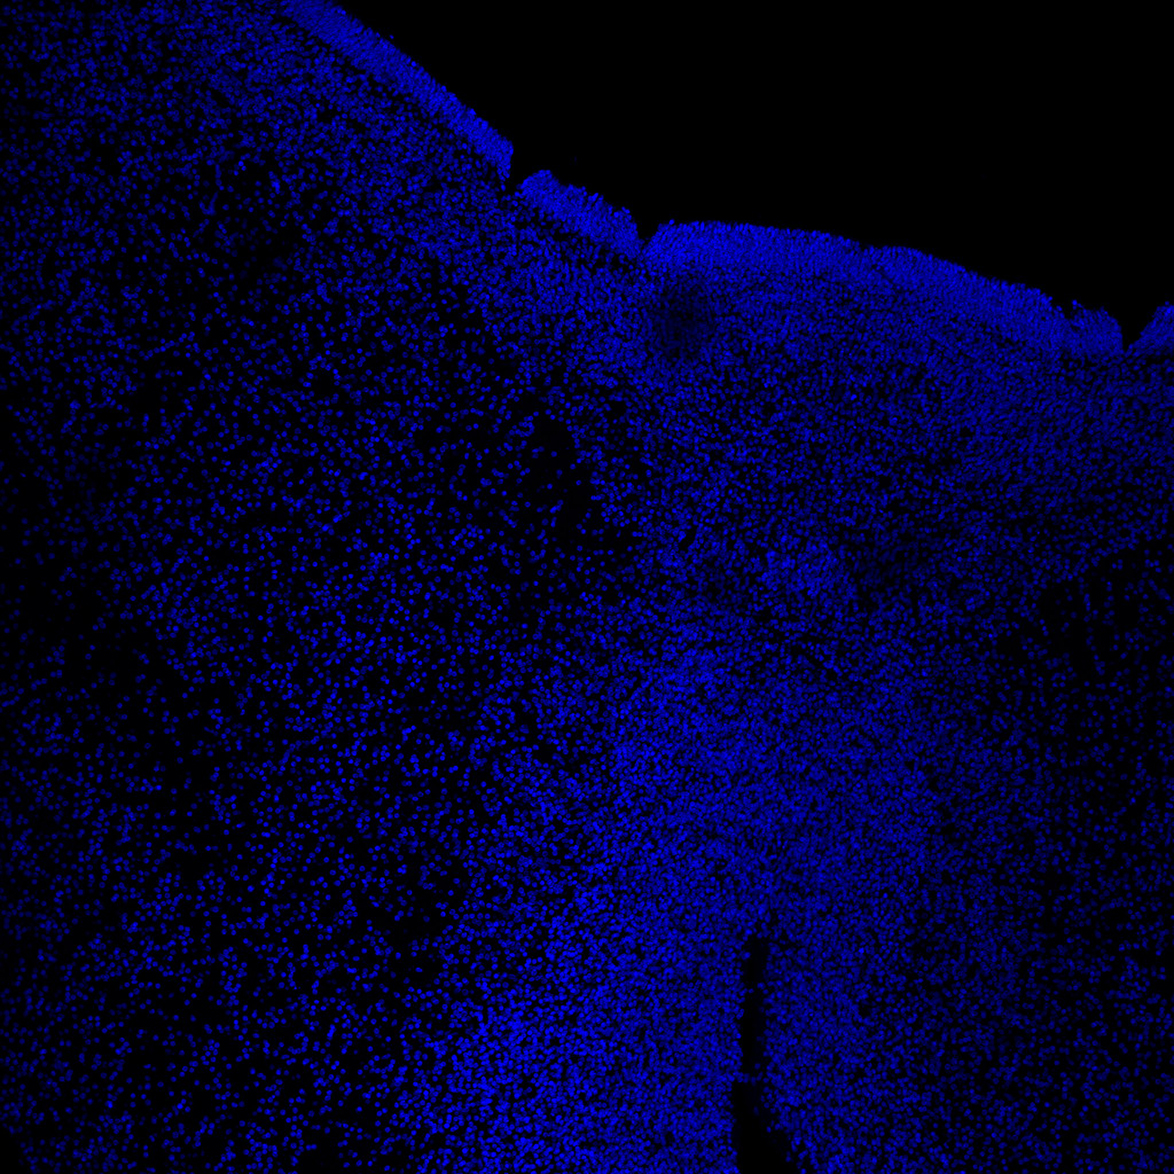

DAPI

11PCW human midbrain